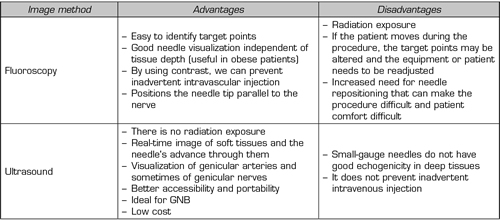

Given the advantages/disadvantages of each imaging method (Table III) and the particularities of each patient, we should choose the best tool when performing block or TRF of the genicular nerves.

Table III. Advantages of disadvantages of fluoroscopy versus ultrasound. GNB (Genicular Nerve Block)